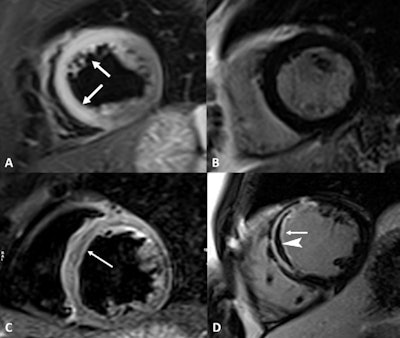

Cardiac MR images acquired from a 44-year-old woman with acute chest pain and chronic cocaine abuse for more than 10 years. Short-axis T2-weighted short tau inversion-recovery (STIR) image (A) demonstrates the presence of transmural edema (arrows) in the anteroseptal and inferoseptal myocardial segments (left descending artery's vascular territory). The late gadolinium enhancement (LGE) sequence in the same cardiac plane (B) did not show gadolinium deposition inside the myocardium. MR images also show an anteroseptal infarction with microvascular obstruction in a 38-year-old man with long-standing abuse of cocaine and troponin elevation. Edema (C) is in the anteroseptal wall (arrow). The short-axis LGE sequence (D) highlights transmural hyperintensity of the anteroseptal wall (arrow) with linear hypointensity (arrowhead) inside the microvascular obstruction. Images courtesy of Radiology: Cardiothoracic Imaging."The real challenge is early diagnosis of cocaine-induced cardiomyopathy and, in particular, its asymptomatic stage," Francone said. "Early diagnosis can indeed have a significant impact on clinical outcome, preventing evolution to heart failure."

More specifically, "cine sequences ... performed on the entire short-axis, four-chamber, and long-axis planes are crucial for evaluation of ventricular function abnormalities," they added. Tissue characterization should include STIR and T2 mapping for edema, as well as T1 mapping, extracellular volume, and LGE sequences to evaluate for fibrosis and necrosis. To diagnose myocarditis, T2-based imaging and T1-based MR imaging criteria are both necessary.